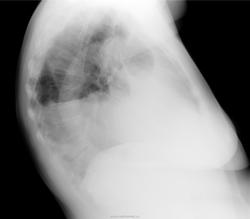

в категории указали "злокачественное образование", для которого зарактерен так называемый "холодный выпот" без температурной реакции. Должно быть затрудненное дыхание. Так как при таком большом выпоте нет смещения средостения в противоположную, следует думать об ателектазе (средняя доля?)

Осумкованный выпот справа. Свободная жидкость в плевральной полости тоже есть. Должна быть одышка. Если есть отёки на ногах - сердечная недостаточность. Ещё много причин, вызывающих скопление жидкости в плевральной полости, в том числе онко, сдавление полой вены.

Как Вам, коллеги, тень в верхней доле справа?Смещения нет, ателектаз, вероятно. компенсирует выпот.Лёгочных жалоб, отёков и лихорадки нет.

Вы абсолютно правы, тут ателектаз + выпот. Выпот за счет Мт в верхних отделах, м.б. и в паракостальную плевру.  Думаю не только средняя доля, а весь центральный бронх.